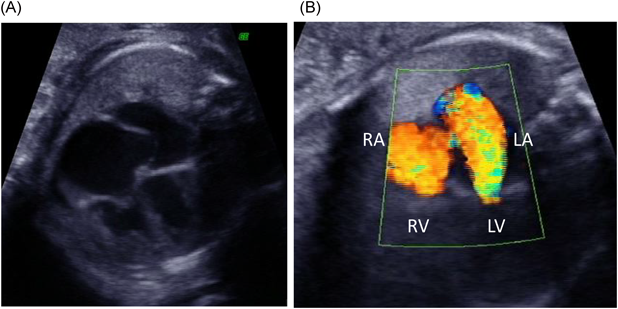

Fig. 3 Electrocardiogram at birth shows biventricular hypertrophy and biatrial overload

心臓超音波検査:僧帽弁輪径10.8 mm,僧帽弁に肥厚(A1–A3, P2)と前尖(A2)に軽度の逸脱あり,MR重度でA1からA3まで幅広く認め左心房後壁へ向かう,乳頭筋は2つ認め腱索に断裂なし,左室流入血流E/A=0.86/1.0 m/s,三尖弁輪径12.7 mm, TR重度で接合不全を認め中央部から後方かつ中隔側へ向かう(Fig. 4),推定右室圧66.0 mmHg, LVEF 57.8%,左室拡張末期径(left ventricular end-diastolic dimension; LVDd)16.5 mm,左室壁厚2.9 mm,動脈管径1.5 mmで左右短絡,冠動脈起始異常なし.

Pediatric Cardiology and Cardiac Surgery 33(3): 215-220 (2017)

Fig. 4 Echocardiogram of the recipient baby at birth

(A) shows left and right atrial enlargement. (B) and (C) show severe mitral regurgitation and tricuspid regurgitation.